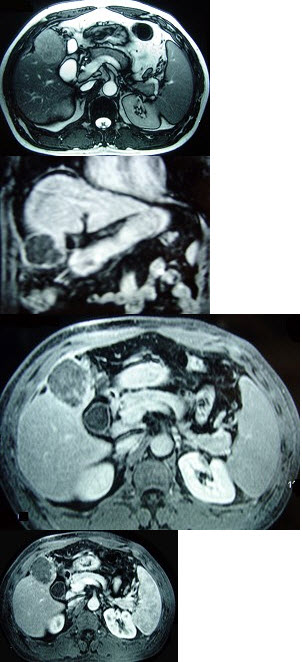

男性,60岁,右上腹胀不适,右肝区叩击痛,影像检查如图,最可能的诊断是( )

A:肝硬化

B:肝硬化、再生性肝癌

C:肝硬化、腹腔间质瘤

D:肝硬化、膈下脓肿

E:肝硬化、结节性增生